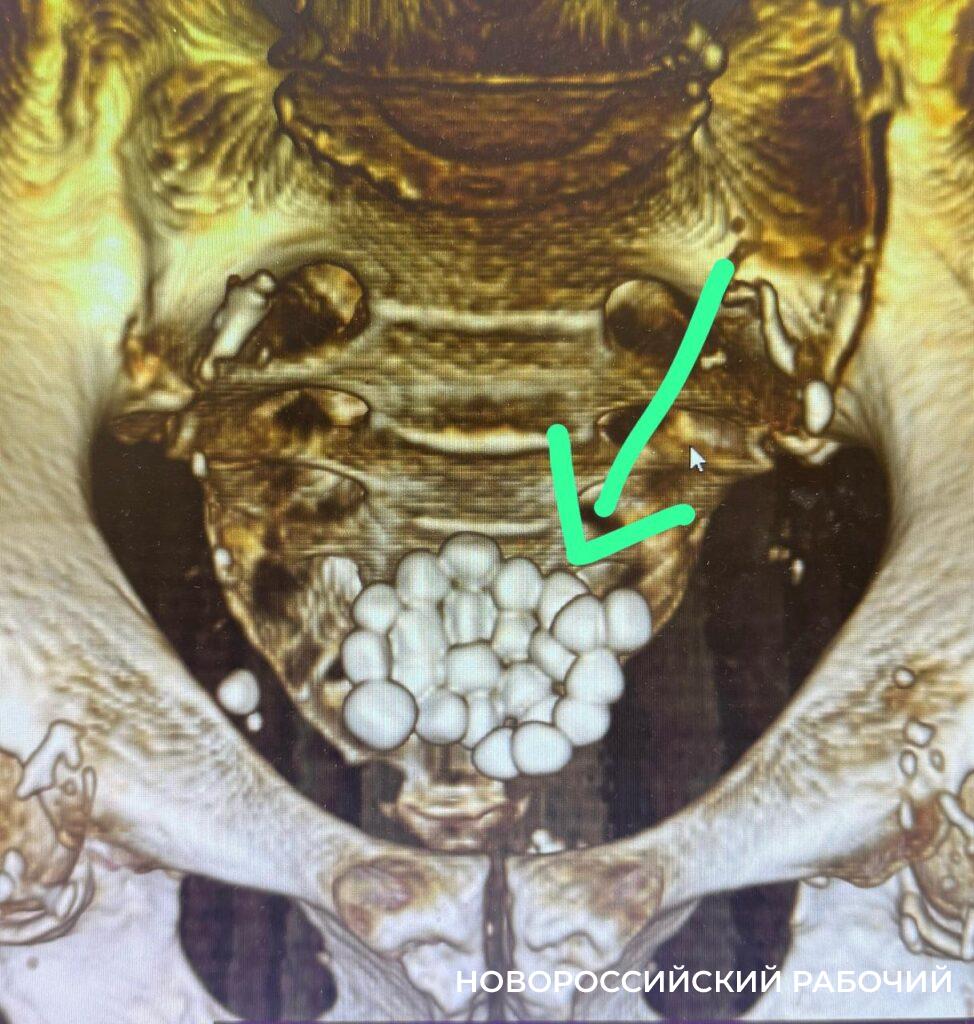

Но у этого больного проявились осложнения — в мочевом пузыре образовалось 24 камня диаметром от 1,0 до 1,5 см. Чтобы спасти пациента, ему одномоментно выполнили 2 операции. Не только удалили все камни, но и провели трансуретальную резекцию простаты.

Благодаря современному оборудованию, хирургическое вмешательство прошло без разреза — эндоскопическим способом. Оперировал пациента заведующий урологическим отделением Игорь Довлад совместно с лечащим врачом Арсланом Темировым, сообщили в пресс-службе горбольницы № 1.